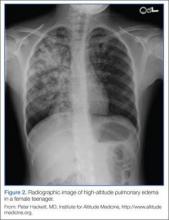

High-Altitude Pulmonary Edema

The most common cause of death from altitude illness is HAPE,12 a form of noncardiogenic pulmonary edema. This condition generally occurs at elevations above 3,000 m. Symptoms begin 2 to 5 days after ascent and progress in a typical pattern. A patient will initially experience a nonproductive cough and dyspnea at rest. The dyspnea worsens, and the cough becomes productive of pink, frothy sputum. Without medical intervention, lethargy, coma, and death may follow.

Symptoms of HAPE generally worsen following a night of sleep at elevation. Physical examination reveals crackles, tachycardia, tachypnea, and hypoxia. Diagnosis requires at least two of the following signs: